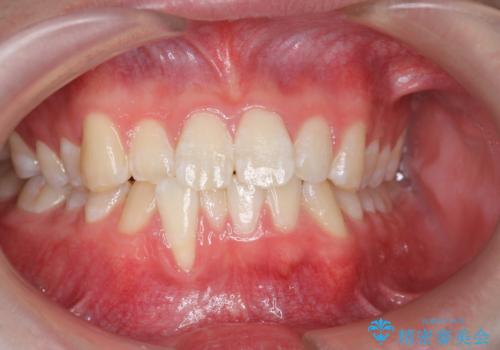

- [ 再生治療・歯周外科・小矯正・セラミック補綴 ] 前歯の歯周病治療- 担当医 大元洋佑 ![[ 再生治療・歯周外科・小矯正・セラミック補綴 ]  前歯の歯周病治療の症例 治療前](https://seimitsushinbi.jp/wp/wp-content/uploads/2022/12/83065c2454a29ed71cf190e15a6106f4-500x350.jpg?v=1671673398) ![[ 再生治療・歯周外科・小矯正・セラミック補綴 ]  前歯の歯周病治療の症例 治療後](https://seimitsushinbi.jp/wp/wp-content/uploads/2022/12/ec16e37ee53325a6f6629b94759f5513-500x350.jpg?v=1671673454)